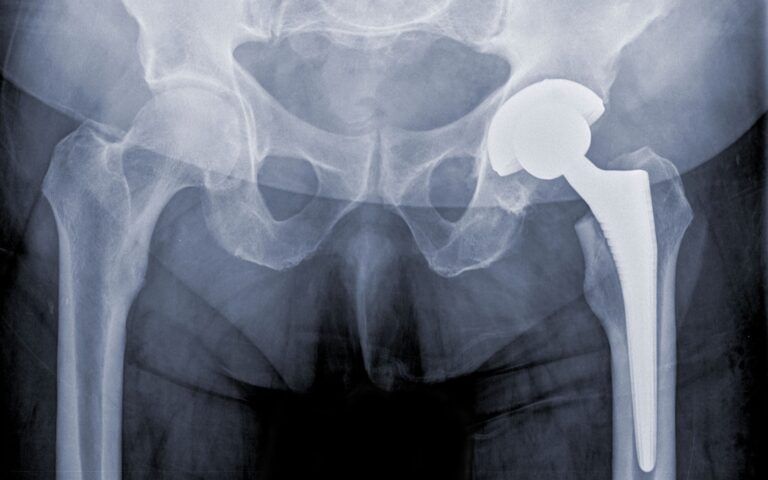

Hip Replacement

Hip replacement is a surgical procedure in which a damaged or worn-out hip joint is replaced with an artificial implant, typically made of metal, ceramic, or plastic components. This operation...